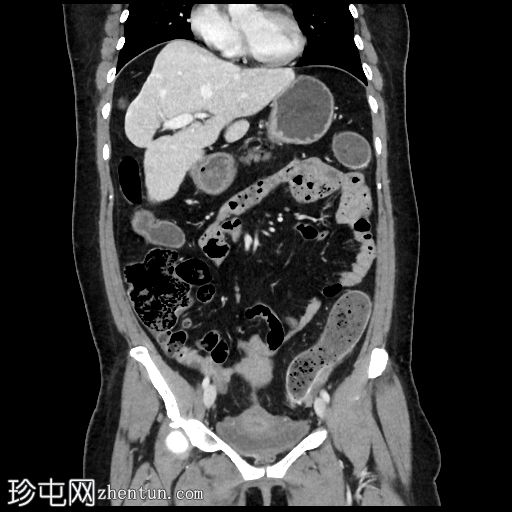

轴位增强扫描(门静脉期)

冠状位增强扫描(门静脉期)

降结肠壁增厚(壁厚达7毫米),15厘米

段,直血管明显,伴脂肪浸润

乙状结肠和降结肠壁钙化